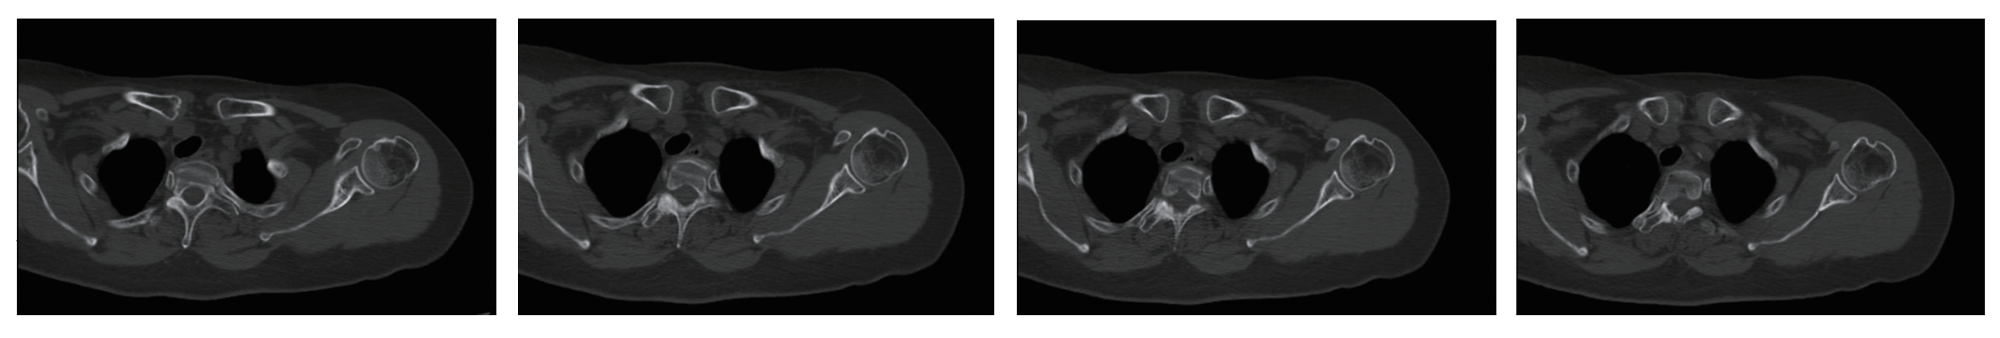

Shoulder Joint